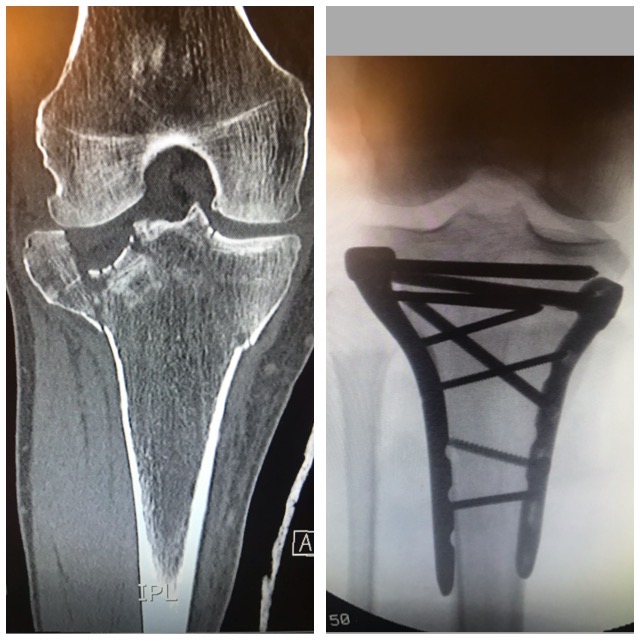

Polven

alueen murtuma

Murtumakuvia

Ennen – Jälkeen